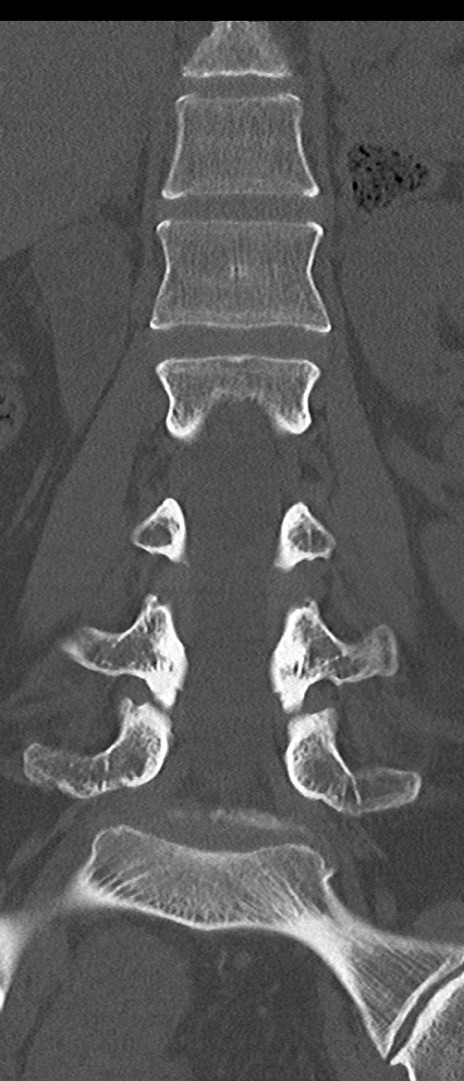

【整形】TIPS症例4 腰椎CT(冠状断像)

腰椎CT